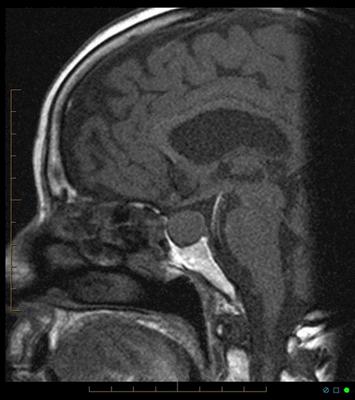

МРТ гипофиза с контрастом. После введения контрастного вещества в гипофизе происходит его накопления и он выглядит светлым. Только участок опухоли не накапливает контрастное вещество и выглятит темным (стрелка).

МРТ гипофиза до и после операции по удалению макроаденомы гипофиза